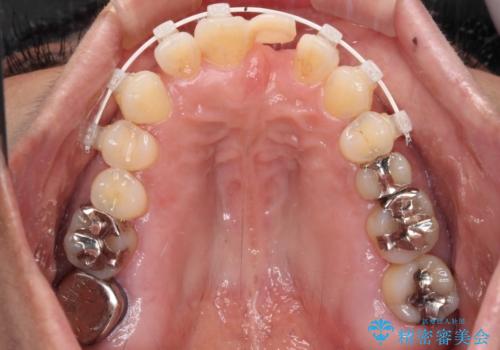

中途半端な矯正治療と前歯の欠損 再矯正とオールセラミッククラウンによる補綴治療

- 矯正治療を行ったものの、隙間やデコボコが多く、欠損している前歯も気になるとのことで来院された患者様です。

当初はセラミック治療だけを希望されていましたが、上下前歯のデコボコが顕著であったため、セラミッククラウンにて治療する前に再度矯正治療を行った方が仕上がりがきれいになると説明し、再矯正を行うこととしました。

矯正治療により前歯横幅のバランスを整えた後に、上顎前歯をオールセラミックブリッジにて補綴治療を行うこととしました。

舌突出癖により、上下前歯が突出して離開してしまったため、舌のトレーニングを徹底的に行いました。